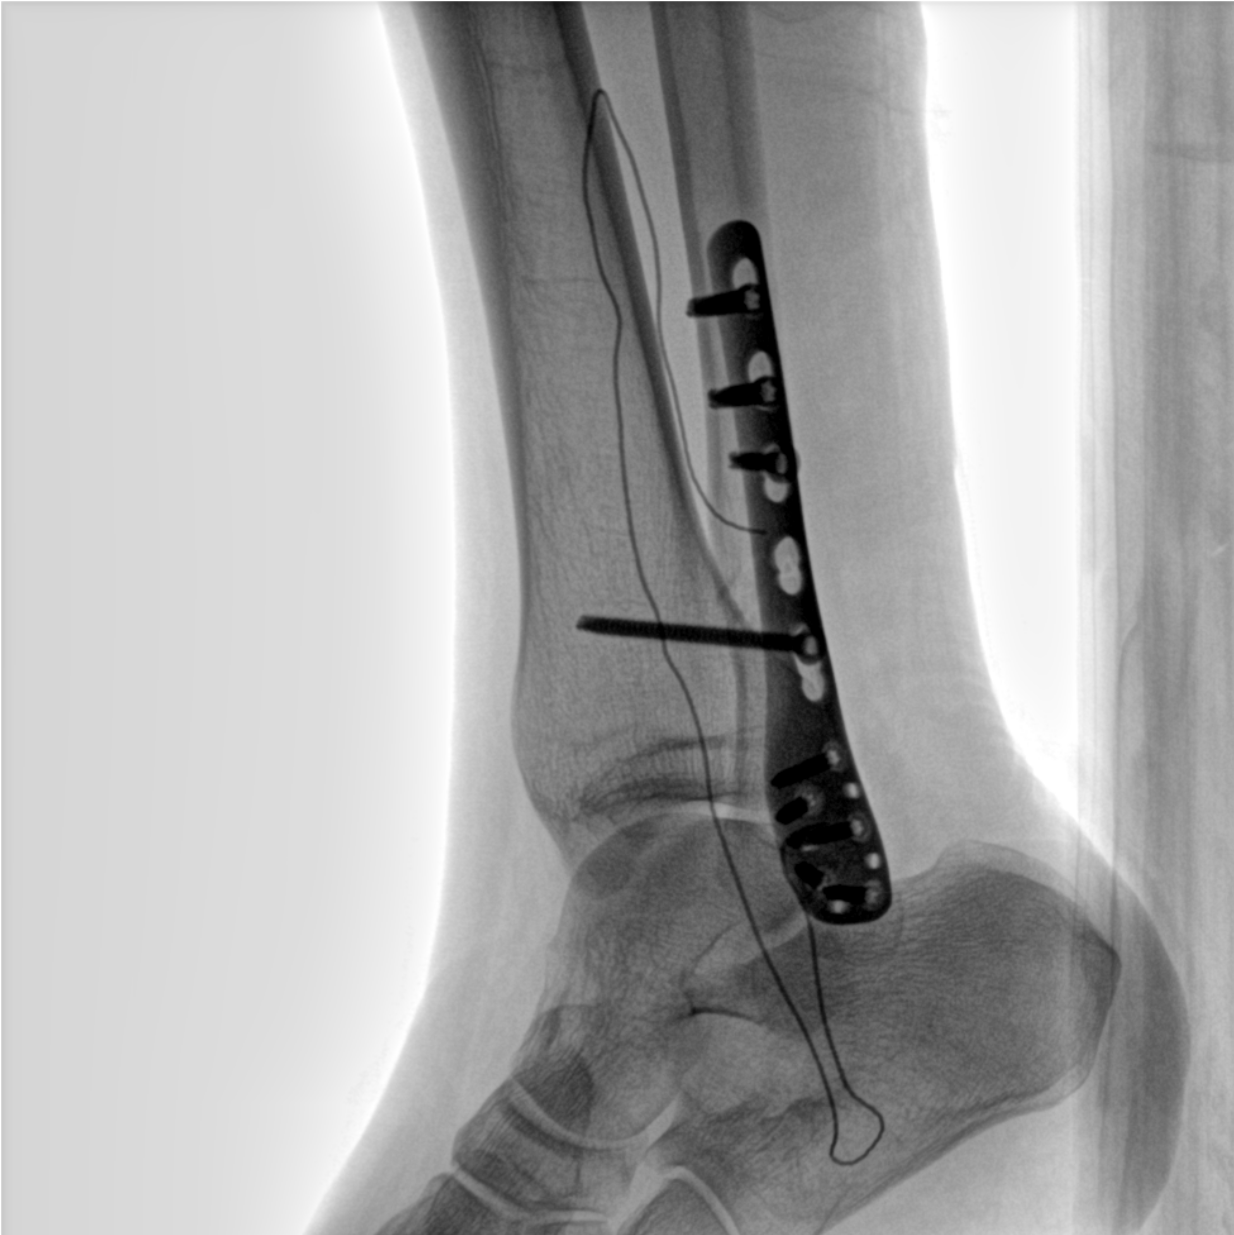

術(shù)中三維成像和橫斷面圖像提供多角度的手術(shù)診斷信息,輔助醫(yī)生進(jìn)行術(shù)中評(píng)估判斷,諸如骨折復(fù)位情況和內(nèi)植入螺釘?shù)某叽绾臀恢茫o助手術(shù)更好地完成。